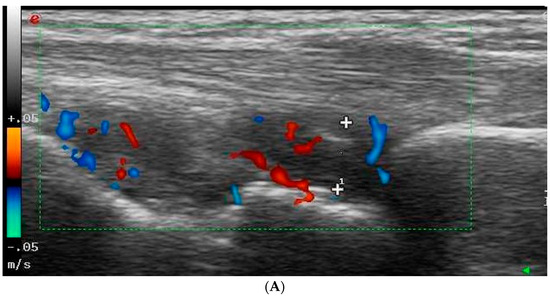

2.3. Ultrasonography Examination